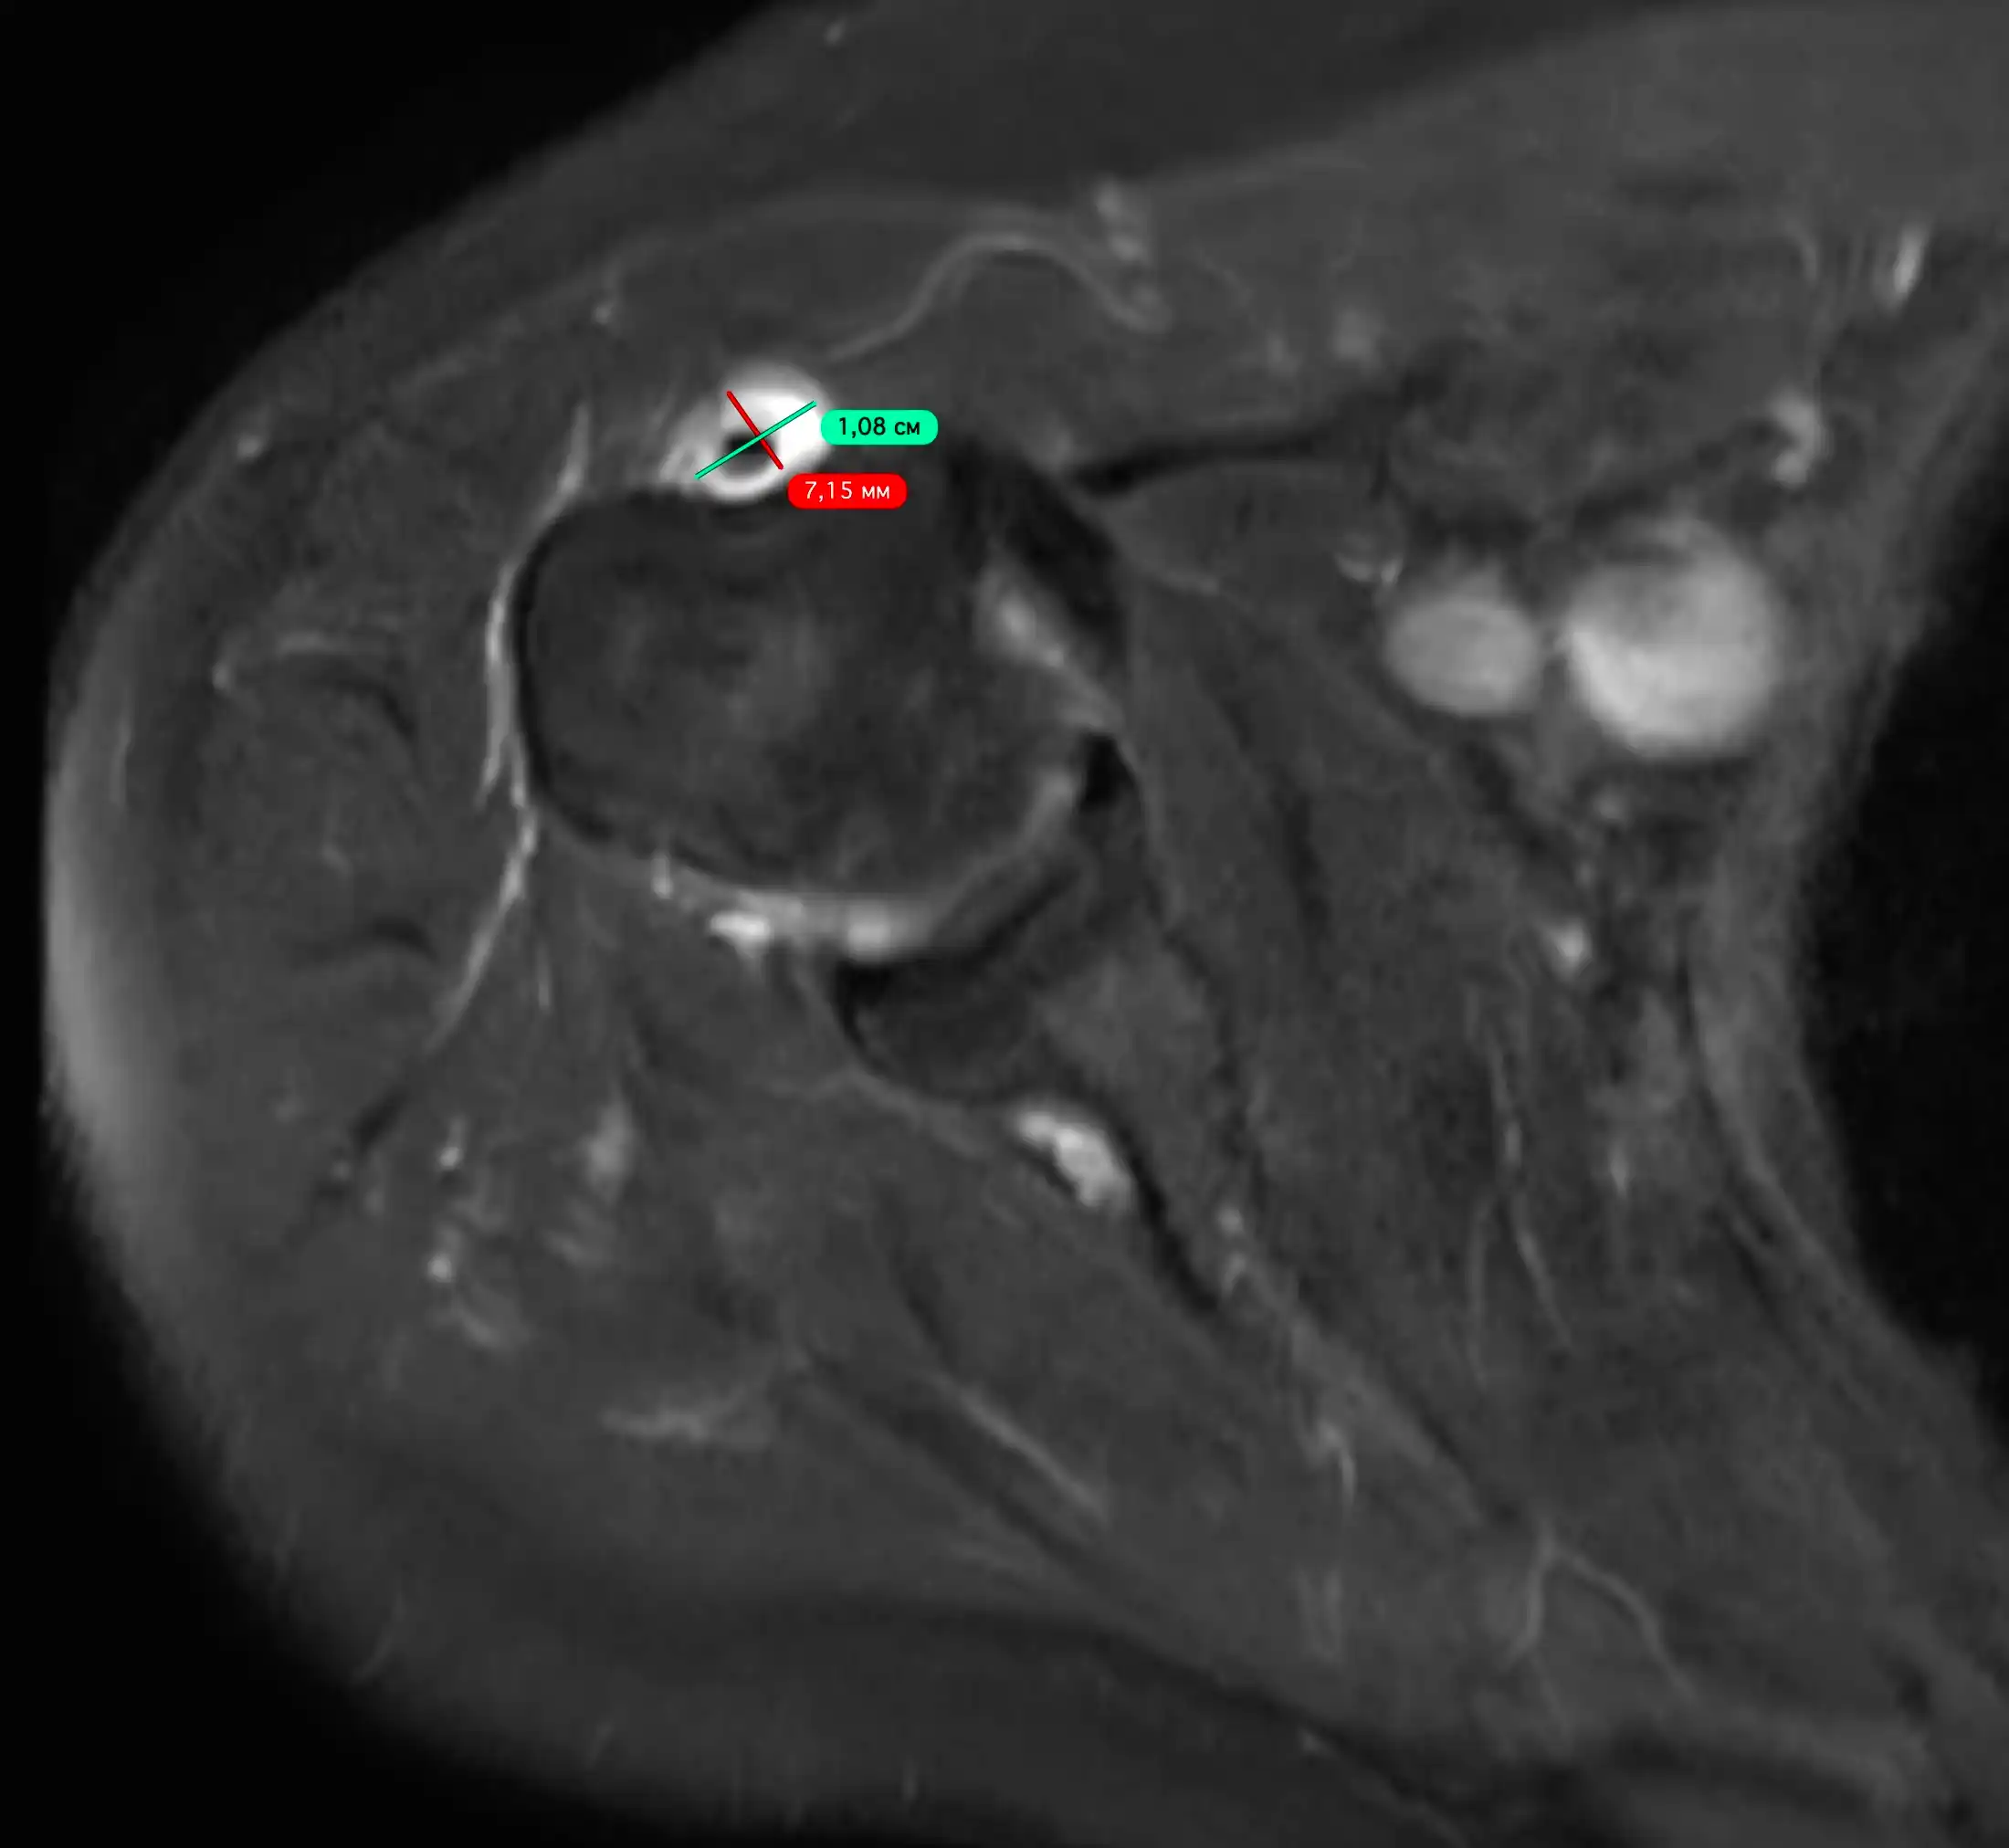

МРТ суглобів (магнітно-резонансна томографія) — це сучасний, безпечний та високоточний метод обстеження, який дозволяє детально оцінити стан хрящів, зв’язок, менісків, сухожиль, капсули суглоба та м’яких тканин.

Що показує МРТ суглобів

Дослідження дозволяє виявити:

- розриви зв’язок

- пошкодження менісків

- запалення сухожиль

- ушкодження хряща

- артрозні зміни

- синовіт

- кісти (наприклад, кіста Бейкера)

- наслідки травм

- пухлинні процеси